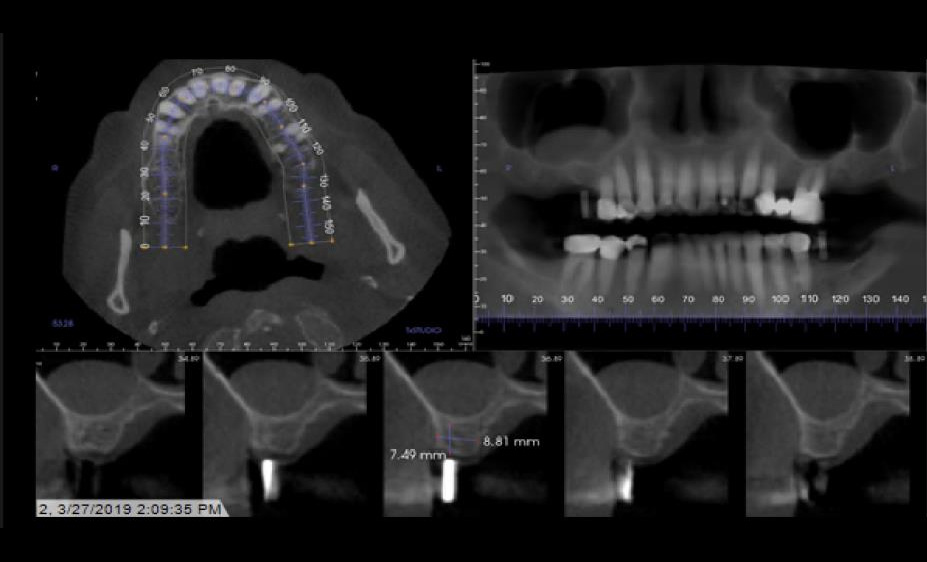

Implant Planning and Restoration #3 and #19

Site #3 Restoration Sequence

Site #19 Restoration Sequence